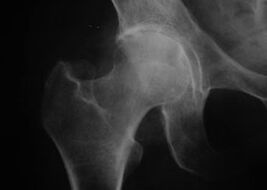

Coxatrosi, artrosi dell'articolazione dell'anca

Con questa malattia si osserva un quadro clinico classico dell'osteoartrosi.

Il primo sintomo della coxartrosi è il disagio all'articolazione dell'anca dopo l'attività fisica.

Con il progredire della coxartrosi, si verificano aumento del dolore, rigidità e mobilità limitata.

I pazienti affetti da una forma grave di coxartrosi proteggono l'arto colpito, evitano di calpestarlo e, da fermi, scelgono posizioni in cui il dolore è meno avvertibile.